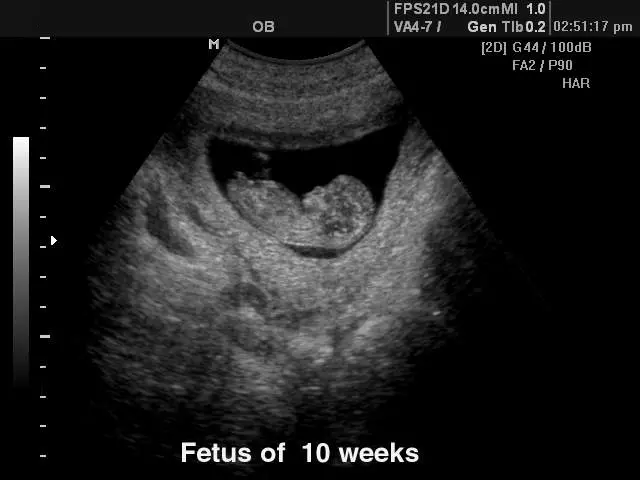

V naši ambulanti se vedno trudimo imeti čimbolj strokoven pristop. To lahko dosežemo le z nenehnim izobraževanjem in spremljanjem razvoja medicinskih postopkov doma ter v tujini. Tako smo se med drugim specializirali za različne preglede, kot je nuhalna svetlina Ptuj.